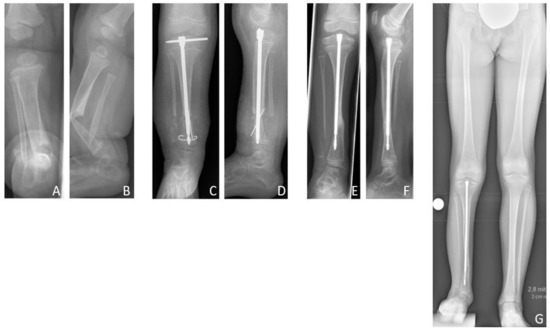

Figure 6. Results Group A. Seven-year-old male patient presenting CPT Paley type 3 (A). Bone transport was performed over a total distance of 50 mm (B,C). After bone docking (D) the external fixator was applied for another three months. After removal of the fixator (E), full bone consolidation was observed after 10 months (F). Five years after reconstruction, at the age of 13 years, the patient showed a remaining LLD of 2.8 cm (G).

The mean age at first surgery was 7.1 (2.8–14.2) years. Excision of the pseudarthrosis and acute compression before intramedullary stabilization was performed in two cases, while three patients solely received intramedullary nailing for stabilization of the pseudarthrosis site. Four patients (80%) were treated with a Fassier-Duval telescoping nail, and one patient (20%) with a TRIGENTM intramedullary nail. Postoperatively a cast was applied for six weeks. Primary bone union was achieved in three patients (60% primary bone union rate). Excision of the pseudarthrosis had been performed in one of the two cases of failed primary bone union. There were no refractures (0% refracture rate), thus the long-term bone union rate was also 60%. Both patients who failed to achieve primary bone union neither achieved secondary bone union, and showed persistent pseudarthrosis at the time of last follow-up.

According to the modified Johnston criteria, three results were grade 1 and two grade 3 (Figure 8).